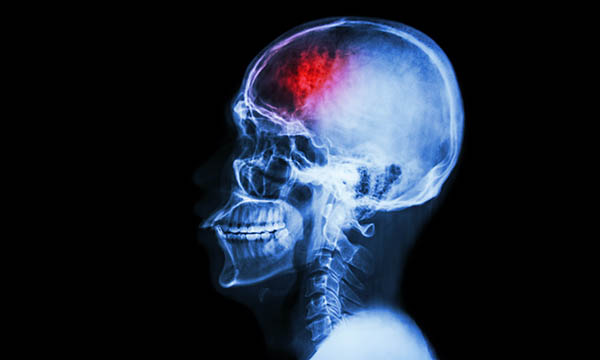

Safety and outcomes of patients with stroke is optimised by specialist care, professor states